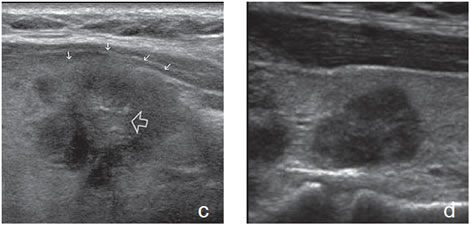

Un nódulo coloideo mixto puede aparecer como un quiste con un nódulo mural isoecogénico, excéntrico, que protruye hacia el lumen simulando una formación papilar, habitualmente vascularizado, que no corresponde a tejido neoplásico (Figura 19a). Si el componente sólido está rodeado por fluido, separado de la pared, y además tiene focos hiperecogénicos, es más difícil confundirlo con un tumor quístico (Figura 19b y c).

Figura 19. a) Nódulo coloideo, que muestra

una proyección de aspecto papilar hacia

el lumen, que corresponde a tejido no

neoplásico, igualmente vascularizado que

el resto del componente sólido del nódulo

(flecha abierta); b) y c) Nódulo coloideo,

predominantemente quístico, con componente

sólido (flecha), que muestra una forma

vegetante completamente rodeada de

coloide, con dos focos puntiformes en el

área más central.